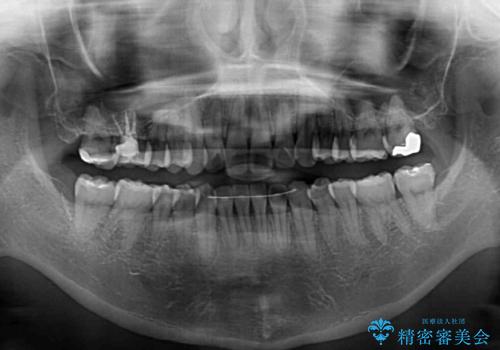

- 前方に傾斜した上下の前歯を気にして来院された患者様です。

唇の閉じにくさや横顔のシルエットが気になるような突出感ではなかったため、インビザラインを用いて、歯列の遠心移動とIPR(歯と歯の間を削る)により前歯の傾斜を改善していくこととしました。

スムーズに終了すると思われましたが、インビザライン矯正独特の奥歯が咬み合わない状態が続き、更には遠方へ転居されたこともあり、治療期間は長引いてしまいました。